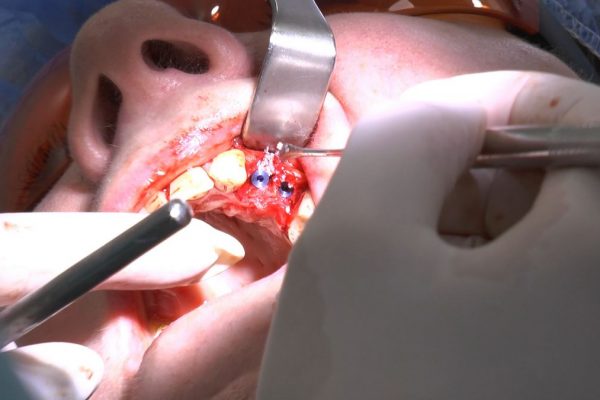

W ostatni weekend czerwca 2018 roku kursanci II Sezonu Preludium Implantologii odbyli piątą, finałową sesję, która w całości podporządkowana była praktyce. W ciągu dwóch dni zabiegowych Lekarze uczestniczący w szkoleniu przeprowadzili szereg zabiegów pod kierunkiem dr n.med. Violetty Szycik. Wszczepili 17 implantów oraz przeprowadzili ekstrakcje i zabiegi regeneracyjne kości. Zabiegi były wykonywane także w sedacji dożylnej z udziałem specjalisty anestezjologii i intensywnej terapii dr Jolanty Grzybowskiej. Preludium implantologii to nowy program edukacyjny dla adeptów implantologii stomatologicznej, którego celem jest wprowadzenie do implantologii poprzez pozyskanie wiedzy w szerokim zakresie i uwzględnieniem szczegółów mających decydujące znaczenie dla powodzenia leczenia implantologicznego. Ale tak jak wszystkie szkolenia w Instytucie Vivadental, w tym wiodące Practiculum Implantologii, zorientowane jest na praktyce i samodzielnym wykonywaniu zabiegów pod kierunkiem Mentora. To najlepsza edukacja w medycynie zabiegowej, a zarazem najlepszy start do implantologii.